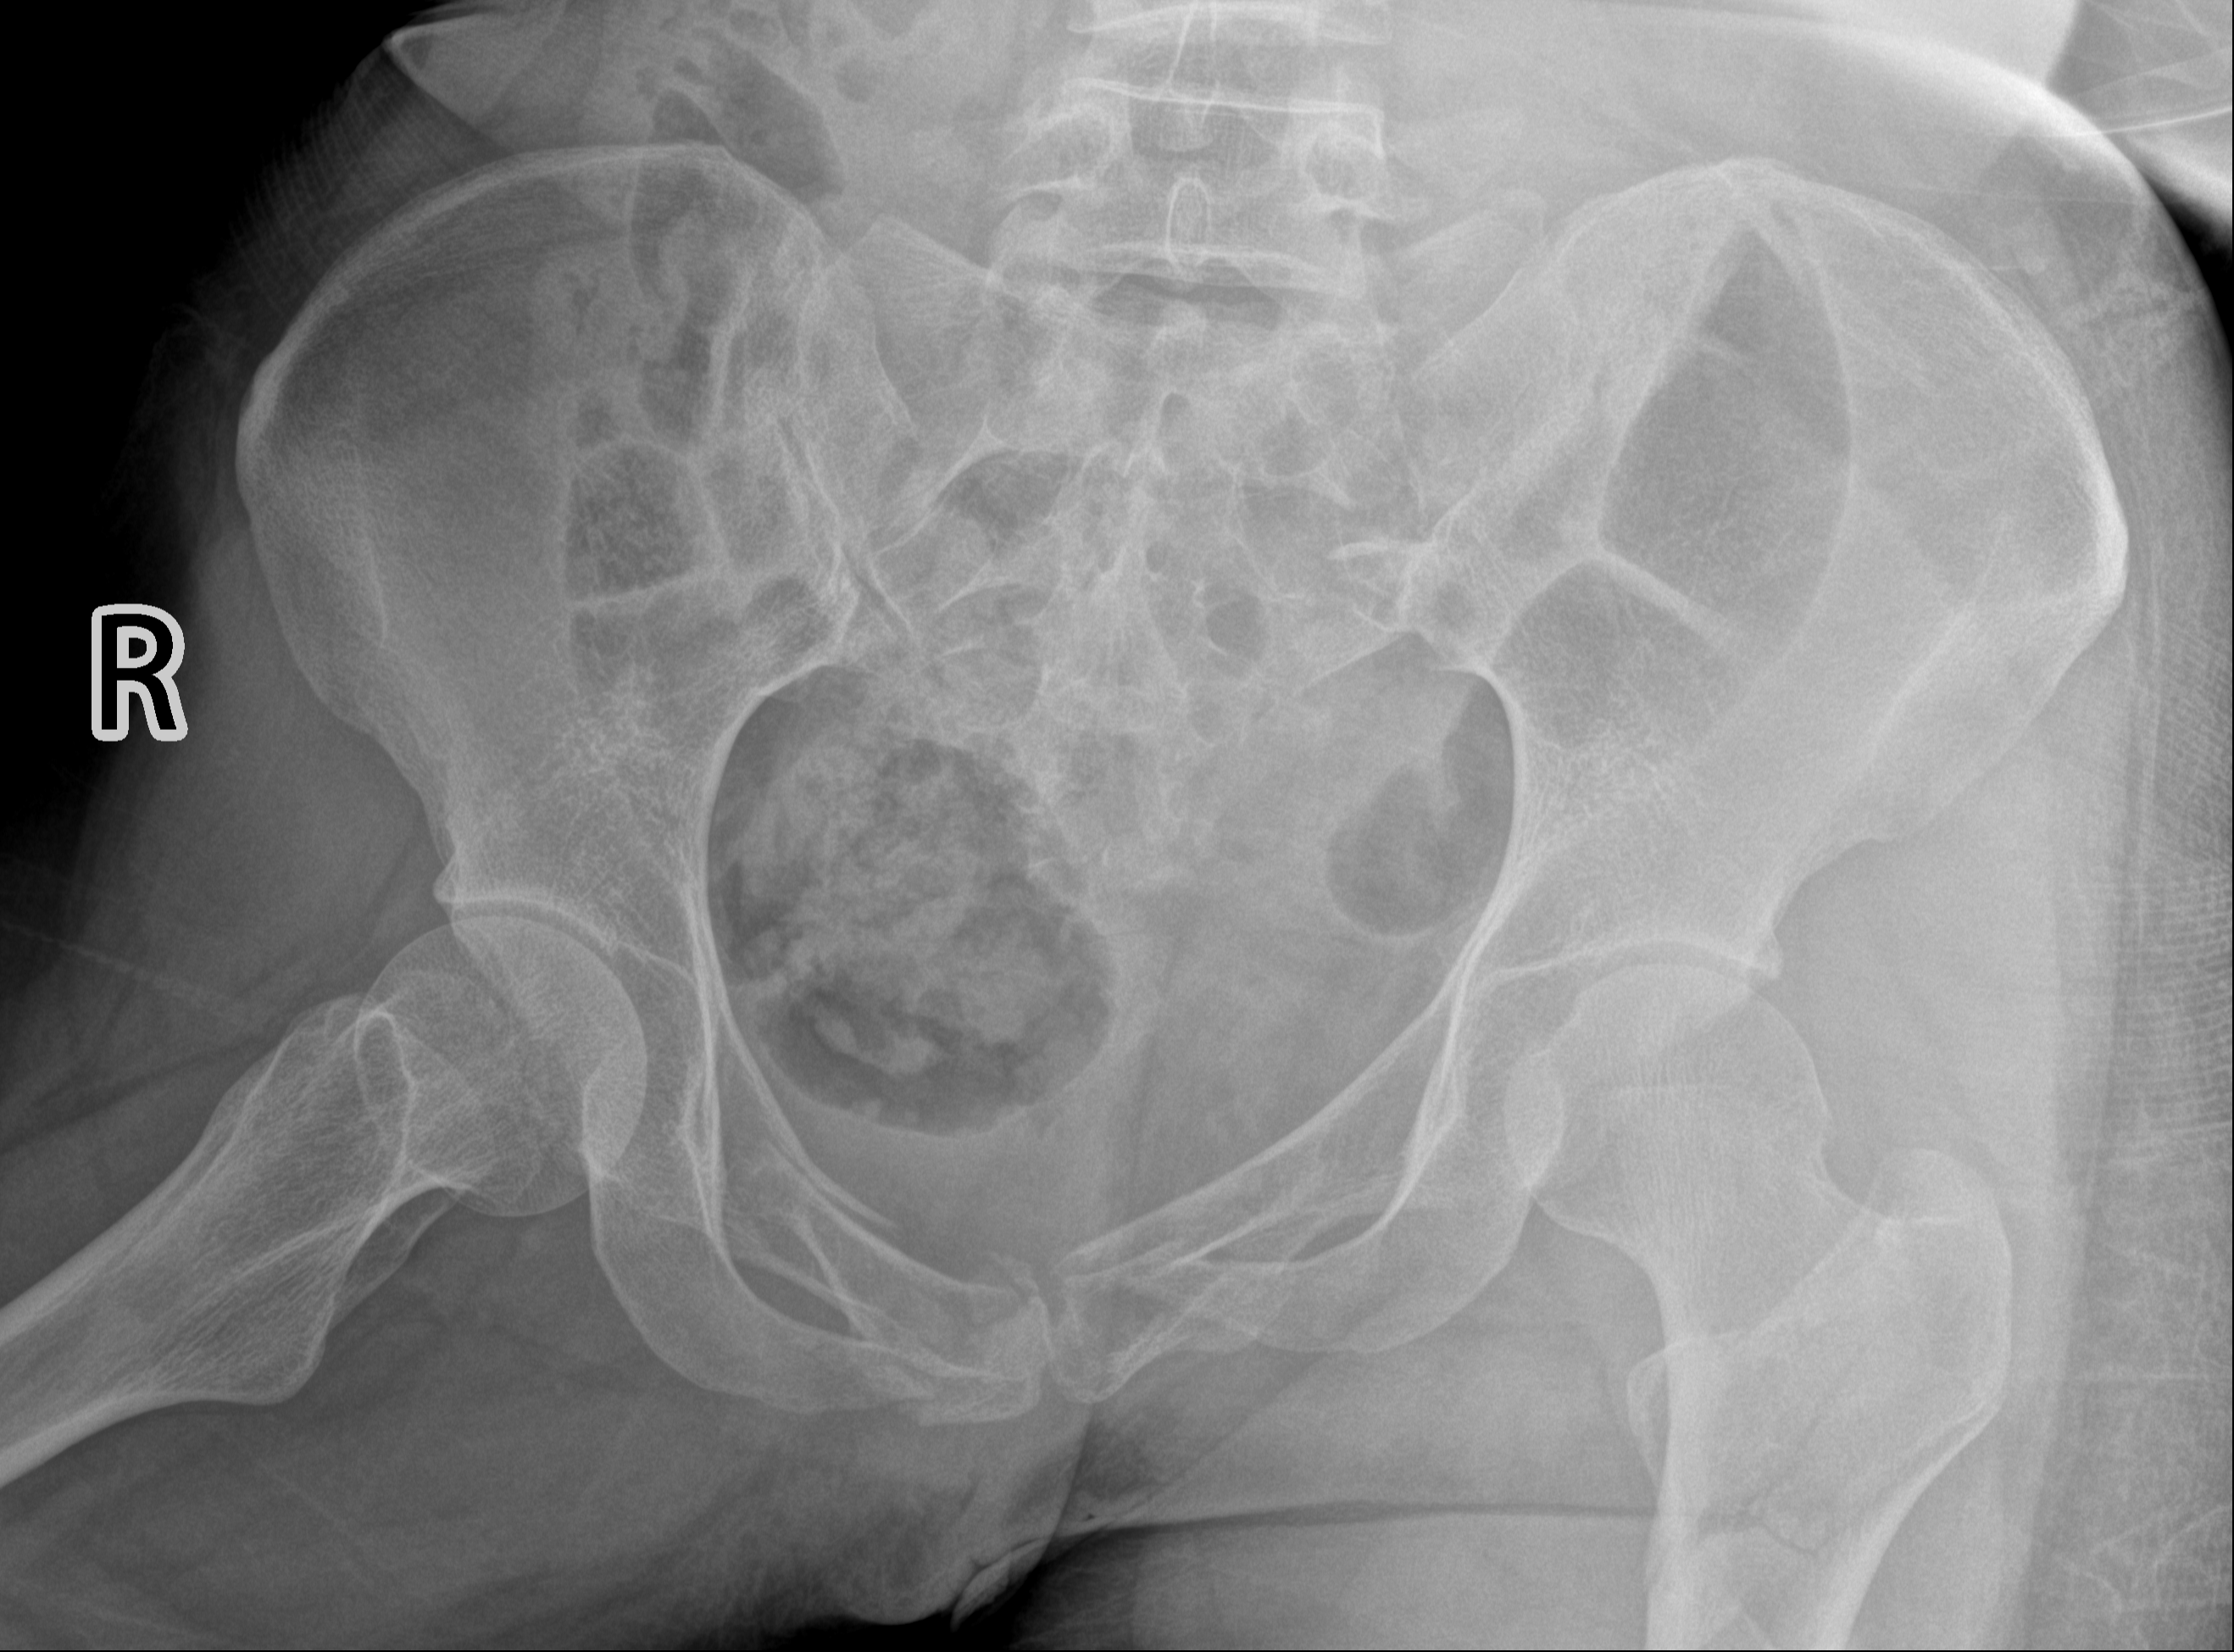

术前